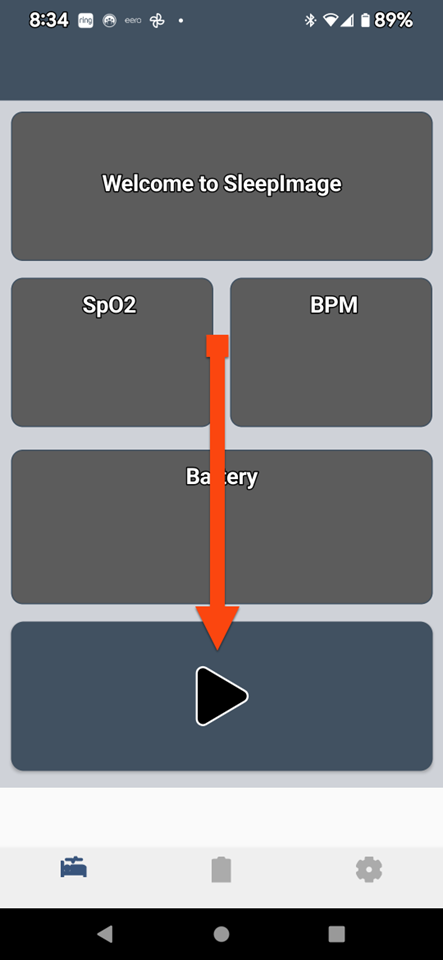

SLEEPIMAGE APP (Android)

SLEEPIMAGE APP (Android)

SLEEPIMAGE APP (Android)

SLEEPIMAGE APP (Android)

SLEEPIMAGE APP (Android)

SLEEPIMAGE APP (Android)

SLEEPIMAGE APP (Android)

SLEEPIMAGE APP (Android)

SLEEPIMAGE APP (Android)

SLEEPIMAGE APP (Android)

SLEEPIMAGE APP (Android)

SLEEPIMAGE APP (Android)

SLEEPIMAGE APP (Android)

SLEEPIMAGE APP (Android)

SLEEPIMAGE APP (Android)

SLEEPIMAGE APP (Android)

SLEEPIMAGE APP (Android)

SLEEPIMAGE APP (Android)

SLEEPIMAGE APP (Android)

SLEEPIMAGE APP (Android)

SLEEPIMAGE APP (iPhone)

SLEEPIMAGE APP (Android)

SLEEPIMAGE APP (Android)

SLEEPIMAGE APP (Android)

SLEEPIMAGE APP (Android)

SLEEPIMAGE APP (Android)

SLEEPIMAGE APP (Android)

SLEEPIMAGE APP (Android)

SLEEPIMAGE APP (Android)